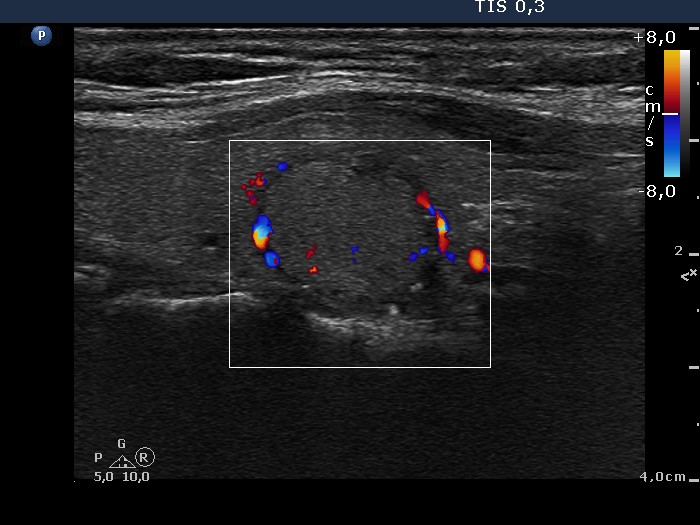

100 consecutive cases of papillary cancer - case 047 (ultrasonographic picture 4)

Right lobe, longitudinal scan

Left lobe, transverse scan, color Doppler mode. The nodule presents perinodular blood flow.